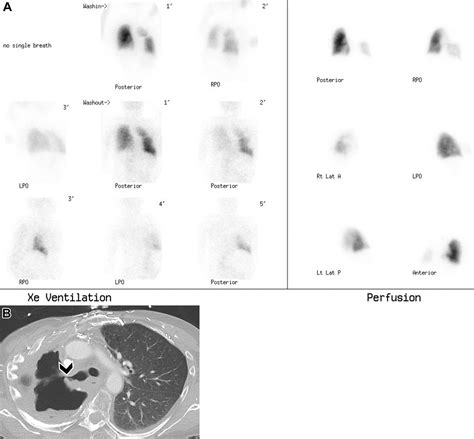

When you experience unexplained shortness of breath, chest pain, or symptoms suggesting a blood clot in the lungs, your healthcare provider may order a Ventilation Perfusion scan, commonly referred to as a V/Q scan. This specialized diagnostic test is a cornerstone of nuclear medicine, designed specifically to evaluate how well air and blood are flowing through your lungs. By comparing two different images—one showing airflow (ventilation) and the other showing blood flow (perfusion)—radiologists can identify areas where a mismatch occurs, which is a classic indicator of a pulmonary embolism or other lung abnormalities.

• The Ventilation Phase: You will breathe in a gas containing a trace amount of radioactive material. This allows the medical team to see how air distributes throughout your lungs.

• The Perfusion Phase: A small amount of radioactive tracer is injected into a vein, typically in your arm. This tracer travels through your bloodstream into the lungs, highlighting areas with healthy blood flow.

After both phases are complete, a special camera called a gamma camera records the images. If the air reaches a part of the lung but the blood does not, it creates a "mismatch," which strongly suggests a blocked vessel, such as a pulmonary embolism.

A radiologist will analyze the ventilation and perfusion images to look for patterns. A normal result shows symmetrical uptake of both the gas and the tracer, indicating healthy airflow and circulation. If the report identifies a "V/Q mismatch," it indicates that air is reaching the alveoli, but blood is not, which usually confirms the presence of an obstruction in the blood vessels. Your physician will integrate these findings with your clinical history, physical exam, and other laboratory tests to formulate a comprehensive treatment plan.